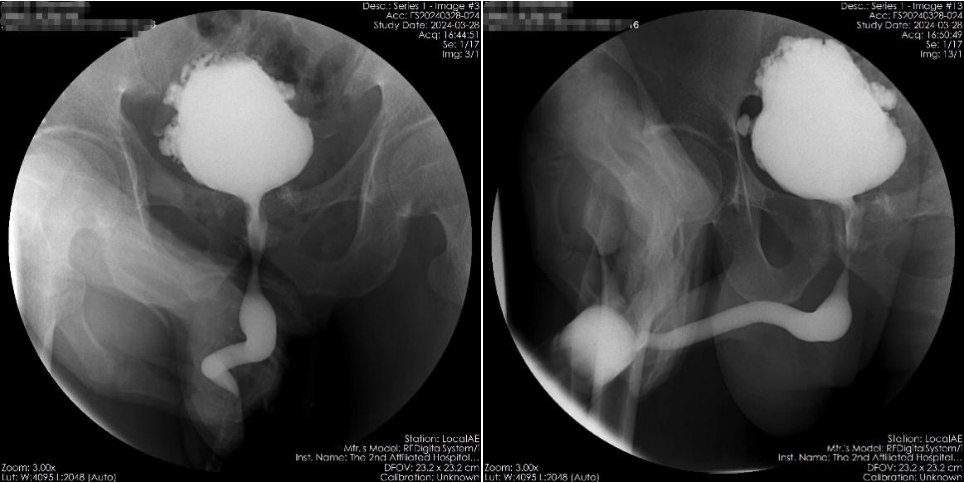

术前尿动力学检查提示膀胱不受控制收缩

膀胱造影检查符合神经源性膀胱表现、排外膀胱出口梗阻